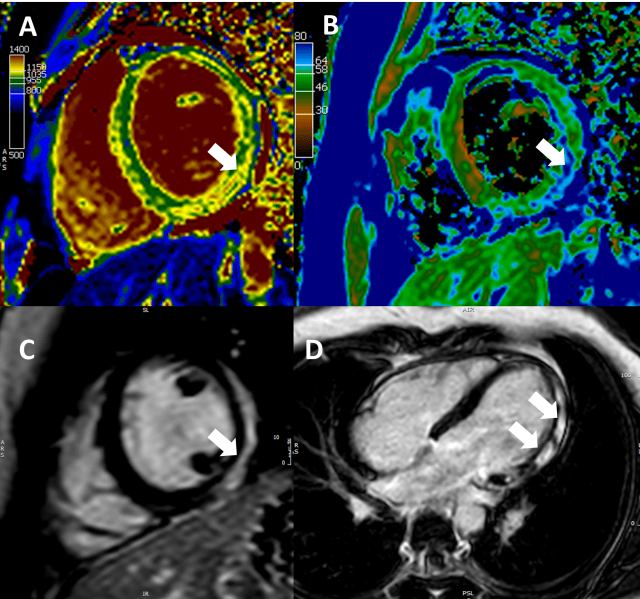

Graphik 1

A bis C: T1-Map (A) und T2 Map (B) sowie passendes Late Enhancement in Kurzachsen mit charakteristischen Gewebeveränderungen (Pfeile). D: Late Enhancement Aufnahme im Vierkammerblick mit charakteristischen epimyokardialen Entzündungsarealen.